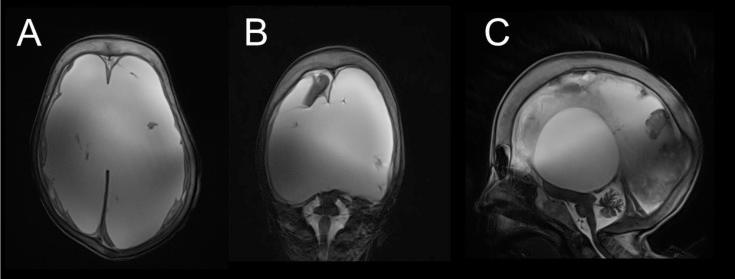

The aim of this study was to perform for the first time the intracranial volumetric analysis of cerebrospinal fluid (CSF) and brain parenchyma in the supratentorial and infratentorial space in a 30-year-old female patient with hydranencephaly and macrocephaly. A head scan performed using a 3T magnetic resonance was followed by manual segmentation of the brain parenchyma and CSF on T2 coronal brain sections. The volume of CSF and brain parenchyma was measured separately for the supratentorial and infratentorial space. The total volume of the intracranial space was 3645.5 cm3. In the supratentorial space, the volume of CSF was 3375.2 cm3 and the volume of brain parenchyma was 80.3 cm3. In the infratentorial space, the volume of CSF was 101.3 cm3 and the volume of the brain parenchyma was 88.7 cm3. In the supratentorial space, there was severe malacia of almost all brain parenchyma with no visible remnants of the choroid plexuses. Infratentorial structures of the brainstem and cerebellum were hypoplastic but completely developed. Since our patient had no choroid plexuses in the supratentorial space and no obstruction between dural sinuses and CSF, development of hydrocephalus and macrocephaly cannot be explained by the classic hypothesis of CSF physiology with secretion, unidirectional circulation, and absorption as its basic postulates. However, the origin and turnover of the enormous amount of intracranial CSF volume, at least 10-fold larger than normal, and the mechanisms of macroencephaly development could be elucidated by the new hypothesis of CSF physiology recently published by our research team.

本研究的目的是首次对一名患有积水性无脑畸形和巨头畸形的30岁女性患者幕上和幕下空间的脑脊液(CSF)和脑实质进行颅内体积分析。使用3T磁共振进行头部扫描后,在T2冠状脑切片上对脑实质和CSF进行手动分割。分别测量幕上和幕下空间CSF和脑实质的体积。颅内空间总体积为3645.5 cm³。在幕上空间,CSF体积为3375.2 cm³,脑实质体积为80.3 cm³。在幕下空间,CSF体积为101.3 cm³,脑实质体积为88.7 cm³。在幕上空间,几乎所有脑实质都有严重软化,脉络丛无可见残余。脑干和小脑的幕下结构发育不全但已完全形成。由于我们的患者幕上空间没有脉络丛,硬脑膜窦和CSF之间没有梗阻,因此脑积水和巨头畸形的发生不能用以CSF分泌、单向循环和吸收为基本假设的经典CSF生理学假说来解释。然而,我们研究团队最近发表的CSF生理学新假说可以阐明比正常情况至少大10倍的大量颅内CSF体积的来源和周转以及巨头畸形的发展机制。